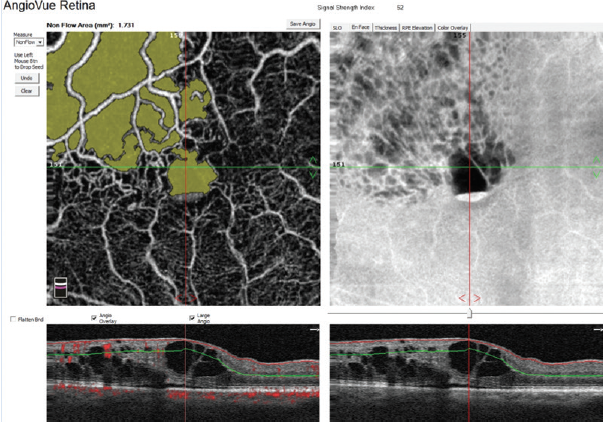

Figure 3. Nonflow area quantification in a patient with central retinal vein occlusion (CRVO).

A helpful step for everyday clinical applications of OCTA has been the development of AngioAnalytics (Optovue), software that provides numerical data about flow area, nonflow area, and vessel density. The flow area measurement tool is useful in the follow-up of choroidal neovascularization (CNV). The operator simply draws the CNV boundary, and the software then calculates the size of the drawn area and vessel area in square millimeters (Figure 2). The nonflow area tool allows clinicians to highlight and monitor the FAZ as well as nonperfused areas in ischemic retinopathies such as DR and retinal vein occlusions (Figure 3). Finally, the vessel density tool automatically calculates the percentage of flow versus nonflow area in an ETDRS grid centered on the macula and in a color-coded vessel density map divided into nine sectors (Figure 4).